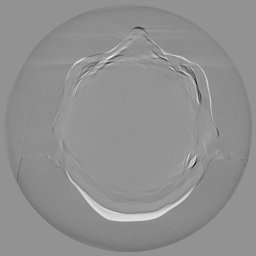

III-C Uncertainty analysis

Classical diffusion models reconstruct images by progressively denoising from an initial Gaussian noise image, a process that inherently introduces uncertainty due to random noise initialization. In contrast, I2SB directly learns a diffusion bridge between two sample distributions, effectively bypassing the need for random noise sampling and thereby reducing reconstruction variability.

To assess the uncertainty of our method, we performed multiple reconstructions using different random seeds. As shown in Fig. 3, the ground truth and representative sampled images are presented in Fig. 3(a) and (b–d), respectively. The mean reconstruction and pixel-wise standard deviation across runs are displayed in Fig. 3(e) and (f). Only minimal differences are observed between reconstructions, indicating that I2SB produces highly consistent results. These findings confirm that, compared with classical diffusion models, I2SB substantially reduces uncertainty across repeated reconstructions.